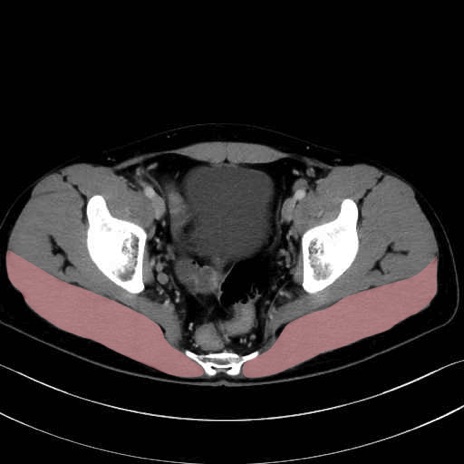

大殿筋 (Gluteus maximus)